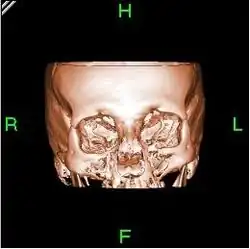

A partir de todas esas imágenes transversales (axiales), un computador reconstruye una imagen bidimensional que permite ver secciones de la pierna (o el objeto de estudio) desde cualquier ángulo. Los equipos modernos permiten incluso hacer reconstrucciones tridimensionales. Estas reconstrucciones son muy útiles en determinadas circunstancias, pero no se emplean en todos los estudios, como podría parecer. Esto es así debido a que el manejo de imágenes tridimensionales no deja de tener sus inconvenientes.

Un ejemplo de imagen tridimensional es la imagen 'real'. Como casi todos los cuerpos son opacos, la interposición de casi cualquier cuerpo entre el observador y el objeto que se desea examinar hace que la visión de este se vea obstaculizada. La representación de las imágenes tridimensionales sería inútil si no fuera posible lograr que cualquier tipo de densidad que se elija no se vea representada, con lo que determinados tejidos se comportan como transparentes. Aun así, para ver completamente un órgano determinado es necesario mirarlo desde diversos ángulos o hacer girar la imagen. Pero incluso entonces veríamos su superficie, no su interior. Para ver su interior debemos hacerlo a través de una imagen de corte asociada al volumen y aun así parte del interior no siempre sería visible. Por esa razón, en general, es más útil estudiar una a una todas las imágenes consecutivas de una secuencia de cortes que recurrir a reconstrucciones en bloque de volúmenes, aunque a primera vista sean más espectaculares.